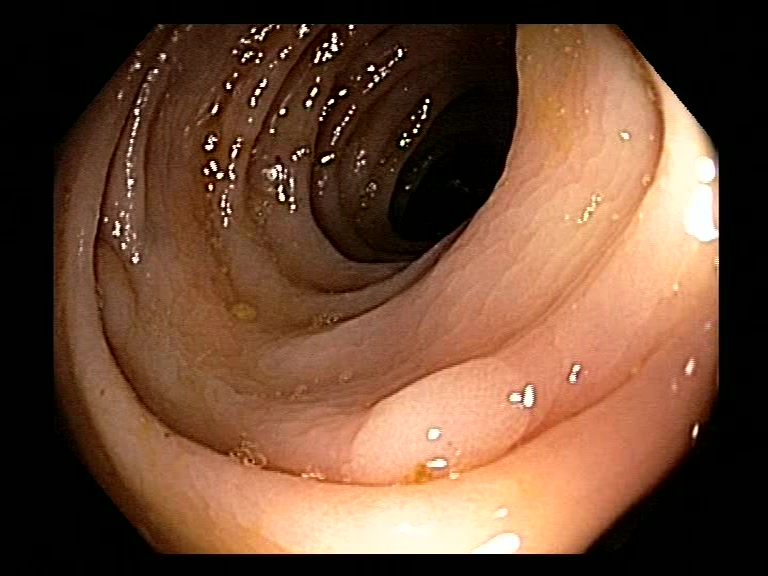

| Lesion | White Light Frame | NBI Frame | White Light Video | NBI Video | Camera Calibration |

| serrated_01 |  |

|

WL.mp4 | NBI.mp4 | cam.xml |